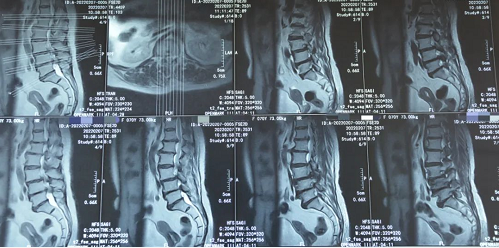

然而,接诊的业务院长韦向荣仔细询问发病过程和查体后,发现病情另有玄机。经过磁共振辅助检查,患者不仅存在颈椎间盘突出和腰椎间盘突出的问题,但更严重的问题出现在胸椎,黄韧带钙化引起的胸椎管狭窄症。“像她这样累积多年的病症,尤其是胸椎、腰椎(T12-L1,L3-4,L4-5)多节段狭窄,在临床上并不是十分的多见。”韦向荣表示。

患者术前影像